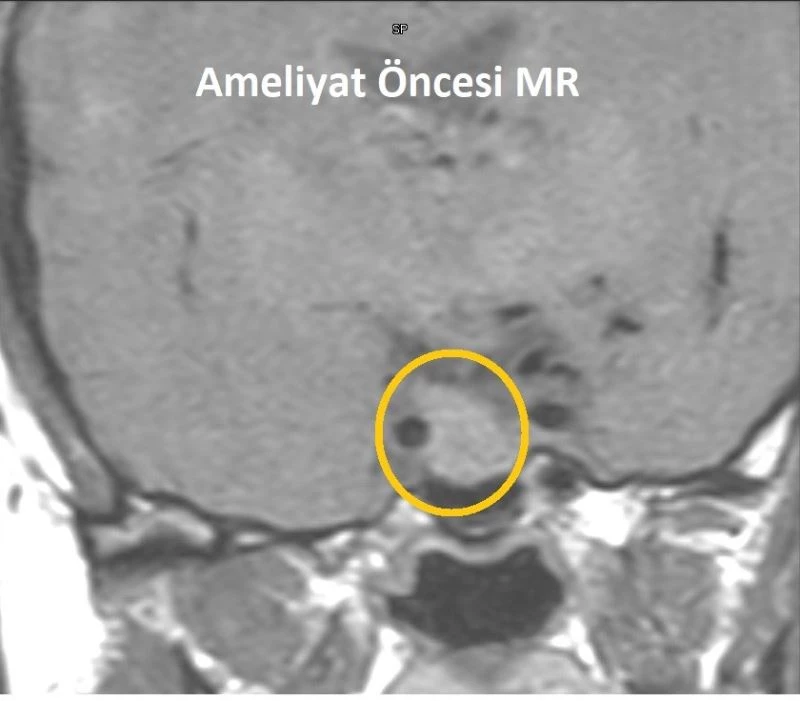

Mersin’de baş ağrıları ve adet düzensizlikleri nedeniyle hastaneye başvuran kadında iyi huylu hipofiz tümörü tespit edildi. 41 yaşındaki Hamde Alahmad, kafatası açılmadan burundan girilerek yapılan ve yaklaşık 3 saat süren operasyonla sağlığına kavuştu.

VM Medical Park Mersin Hastanesi’nde adet düzensizlikleri ve baş ağrıları nedeniyle yapılan tetkiklerde hipofiz bezi yerleşimli yaklaşık 2 santimetre boyutlu adenom (iyi huylu hipofiz tümörü) tespit edilen 41 yaşındaki Hamde Alahmad, başarılı bir ameliyat ile tedavi edildi. Kafatası kemiği açılmadan burundan endoskop ve nöronavigasyon gibi yüksek teknolojiler kullanılarak gerçekleştirilen ameliyatı, hastane dışından Kulak Burun Boğaz Uzmanı Prof. Dr. Hayrettin Cengiz Alpay, VM Medical Park Mersin Hastanesi Kulak Burun Boğaz Uzmanı Op. Dr. Aykut Bozan ve Beyin Cerrahisi Uzmanı Prof. Dr. Bora Gürer ile Op. Dr. Ramazan Fesli başarılı bir şekilde gerçekleştirdi.